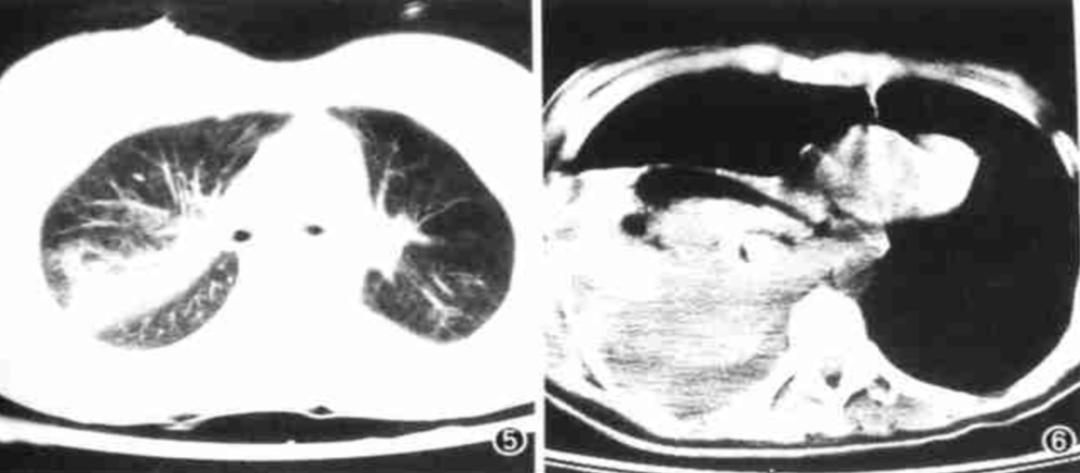

4)边缘型:挫伤病灶沿肺叶边缘分布(图10) 。

5)实变型:肺挫伤严重,病变渗出明显,肺叶完全实变(图11)。

图10(左):边缘型;图11(右):实变型

其影像学特点包括(图13):

(1)胸膜改变(早期即可出现):①胸膜斑:双侧胸壁中、下部对称性三角形阴影,部分有钙化;②胸膜增厚、粘连;③渗出性胸腔积液:双侧多见,可为血性。(2)肺部改变:①网状阴影(主要改变):中下肺细网、粗网、蜂窝状改变;②融合灶:双肺基底部,边界不清,范围不大的片状阴影;③肺门结构紊乱,密度增高,但无肺门淋巴结肿大。

图13:石绵肺的典型影像学表现(资料)